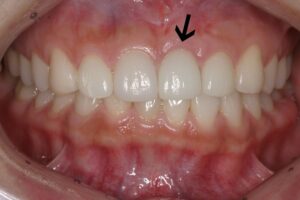

브릿지로 앞니를 치료하면 수술없이 간편하게 치료할 수 있지만 치아를 뽑은 자리 치조골에 자극이 사라져 시간이 경과하면서 뼈와 잇몸이 사라집니다. 그래서 빠진 치아부위가 꺼져서 웃을 때 그 부분이 검게 보이게 됩니다.

(앞니브릿지 웃을 때 검게 보임)